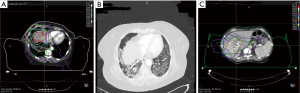

A summary of the treatment toxicities is presented in Table 2. Most patients had at least grade one acute RT toxicities (89.3%), and five had grade two acute RT toxicities (17.9%). Seven (25%) of the patients who had acute toxicities were diagnosed with extrahepatic CCA. Two patients experienced long-term RT toxicities. One patient with extrahepatic CCA had grade two hepatic impairment (3.6%) possibly attributable to RT and another patient with intrahepatic CCA had grade three pneumonitis (3.6%) likely attributable to RT. The RT plans for these two patients were reviewed to attribute them to RT (Figure 1). For the patient with pneumonitis, mean dose to the full right and left lungs was 19.8 and 9.1 Gy, respectively (Table 3). Furthermore, the full right lung V20 was 39% and full left lung V20 was 19% (Table 3). For the individual who developed hepatic impairment, the mean normal (liver-GTV) dose was 23.74 Gy and the patient received 15 fractions of RT (Table 3). One patient experienced late gastric pain; however, on endoscopic evaluation, no ulcers were identified. Further, on review of the dose-volume histogram, there was no significant dose to stomach, suggesting RT was not responsible for this side effect. Overall, the main toxicities related to systemic therapy regimens were fatigue (50%), nausea (42.9%), and thrombocytopenia (35.7%) (Table 2). Additionally, other immune-related toxicities included dermatitis (3.6%), colitis (10.7%), and pneumonitis (7.1%) (Table 2).

Most (89%) patients did experience some acute low-grade RT toxicities, although significant toxicities were rare, with no grade three events. However, late RT toxicities were present, with one patient experiencing grade two hepatic impairment and another patient experiencing grade three pneumonitis. Importantly, this toxicity profile is similar to prior reports that established hypofractionated RT as a viable treatment prior to the routine incorporation of immunotherapy in the treatment landscape of CCA. For example, Smart et al. reported 95% incidence of any grade RT toxicity and one instance of radiation-induced liver disease (RILD) among patients receiving hypofractionated RT for intrahepatic CCA (13). Similarly, in the initial report by Tao et al., our group observed low rates of significant toxicity, including cholangitis (4%), and gastric bleeding (1%), with no observed RILD (8). Overall, therefore, the early outcomes reported here do not provide substantial evidence that risks of RT are significantly higher in the era of immunotherapy, although this observation warrants further confirmation, ideally in prospective multi-institutional cohorts.